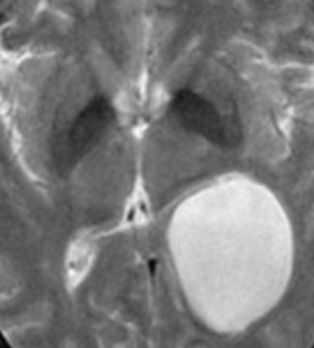

МРТ головного мозга. Корональная Т1-взвешенная МРТ. Многокамерные эхинококковые кисты.

Киста кармана Ратке представляет собой редко встречающееся образование из остатков эмбриональной эктодермы (щель Ратке), расположенное между долями гипофиза. Выявляется в любом возрасте, но чаще в 50-60 лет. Клинические проявления связаны с масс-эффектом. При МРТ головного мозга выявляется небольшая (3-5мм) киста с четким контуром, без отека вокруг, однородная по структуре. Сигнал на МРТ головного мозга зависит от содержимого. При серозном содержимом сигнал типично жидкостный, при мукоидном киста светлая на Т1-взвешенных МРТ головного мозга. В 70-80% случаев внутри кисты выявляется неконирастирующийся узелок («пятно») - признак патогномоничный для кисты кармана Ратке. В редких случаях киста достигает больших размеров и даже выходит за пределы седла. Стенка кисты иногда усиливается при МРТ головного мозга с контрастированием. Дифференциальная диагностика при МРТ головного мозга должна проводиться с арахноидадьной и эпидермоидной кистами, тератомой, кистозной аденомой гипофиза и краниофарингиомой. Иногда при МРТ головного мозга киста кармана Ратке напоминает “пустое” турецкое седло. При маленьких размерах кисты ее на до дифференцировать на МРТ с микроаденомой гипофиза.